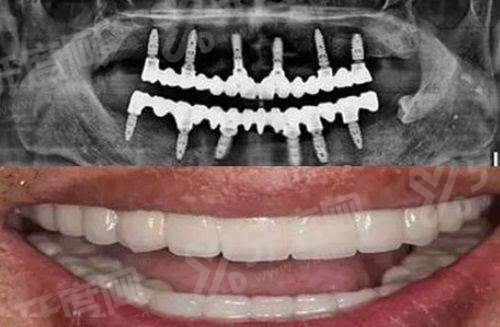

为了让大家更直观地了解成效,分享一个真实实例:72 岁的张大爷,全口牙齿脱落多年,只能吃流食,身体日渐消瘦。他在子女陪同下来到盐城双宝,经过检查发现牙槽骨吸收重度。医生为他制定了"All-on-6"全口种植方案,选用瑞典诺贝尔植体。手术仅用时 3 小时,张大爷当天就戴上了临时固定桥。复诊时他激动地说:“现在啃苹果都没问题,脸上皱纹都舒展开了,这钱花得真值!”这个实例生动诠释了盐城双宝口腔医院做全口种植牙多少钱背后的超值体验。www.yadoo.cn